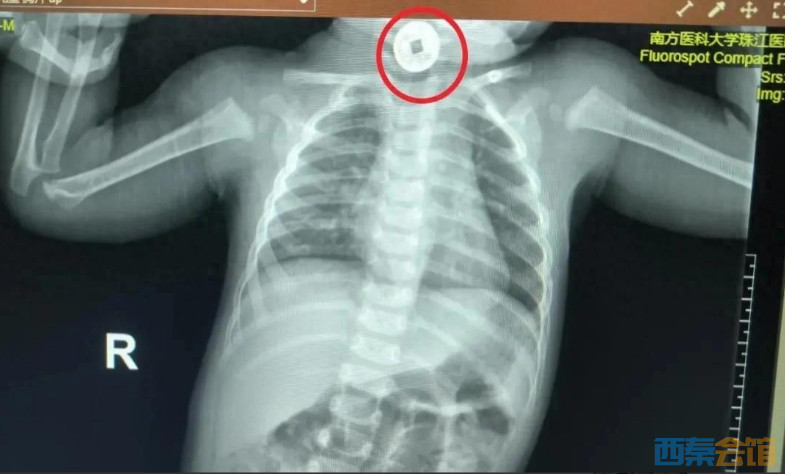

医护人员立刻启动紧急检查:通过影像学确认,一枚直径约2厘米的圆形祈福币卡在宝宝食道上段,距离咽喉仅3厘米。

这个位置很关键:食道上段狭窄,若异物滞留时间过长,可能压迫气管引发窒息,还可能损伤食道黏膜导致出血、感染。